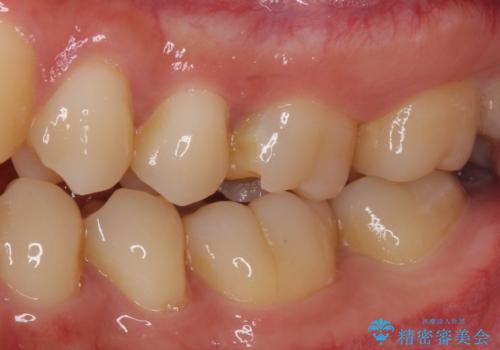

- 食事中にしばしば痛みを感じるとのことで来院された患者様です。

診査をしたところ、レントゲン写真よりとても大きなむし歯があることが分かりました。

虫歯が歯髄腔(神経の部屋)に達している可能性が非常に高かったため、炎症を起こしている神経組織を部分的に切除し、歯根部分の神経組織を保存する治療法が望ましいと考えられました。